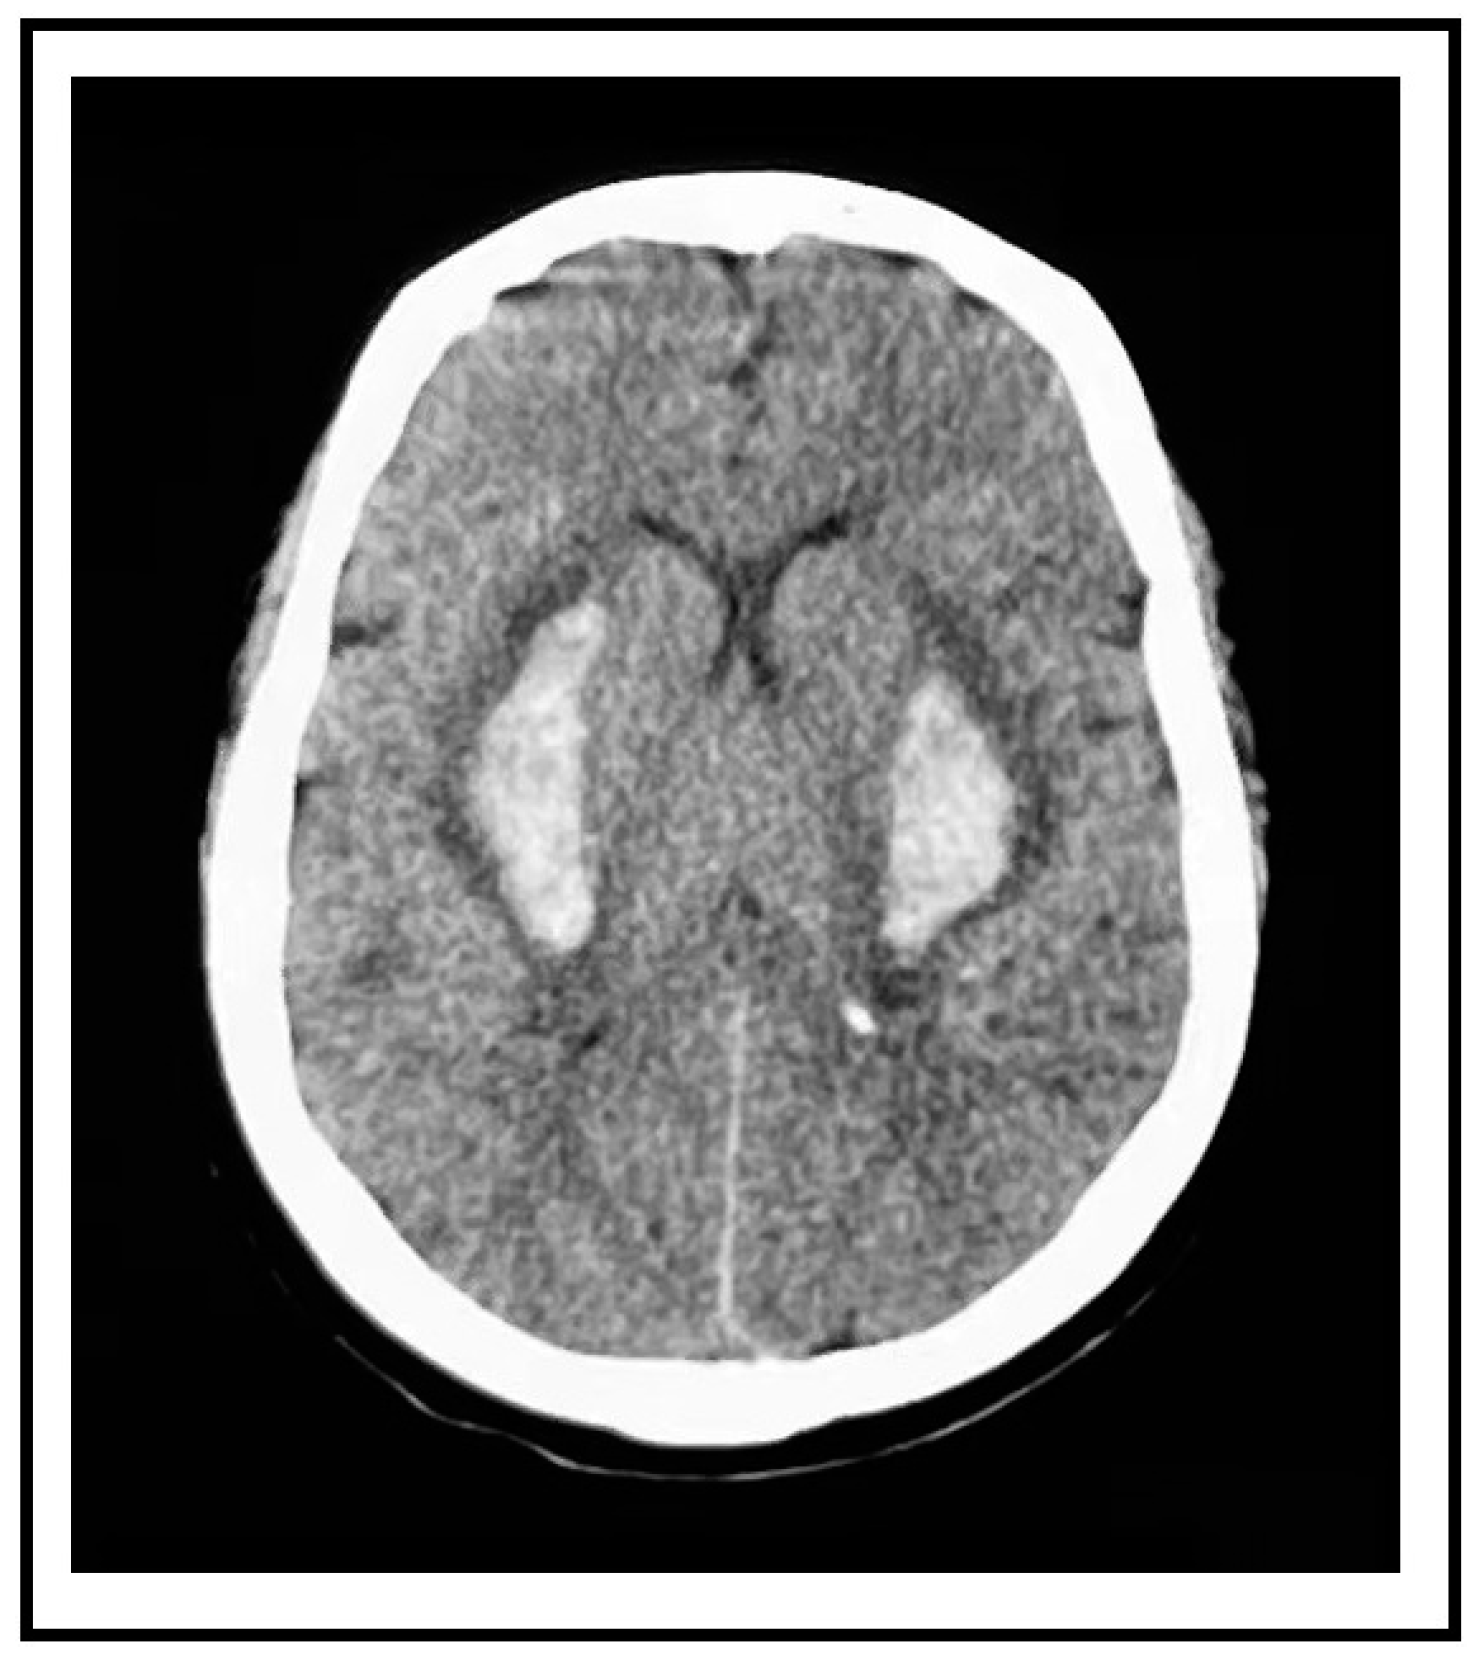

A 59-year-old female presented to the emergency department with a sudden loss of consciousness and complete quadriplegia. Her bilateral psychological reflection was weakened and the reflex of Babinski’s sign was positive. She had a history of poorly controlled and irregularly treated hypertension. Immediate non-contrast computed tomography (CT) revealed bilateral putaminal hemorrhages that were symmetrical (right side 10.7 mL, left side 11.37 mL). These two paired hemorrhages mirror each other in position and shape (

Figure 1). The magnetic resonance imaging of the head and computed tomography angiography of the head and neck did not show aneurysms, vascular malformations, vascular amyloidosis, or tumors (

Our patient’s first symptom was the loss of consciousness without any unilateral local neurological symptoms. Her CT scan revealed bilateral hematomas with almost identical morphological characteristics. No prior research has documented such a mirror image of spontaneous cerebral bleeding. The short time lag and the mirror image are supportive evidence of our hypothesis that the distribution of lesions related to hypertension may be symmetric, which makes it more likely for bilateral ruptures to occur at the same time or over a very short amount of time. Additionally, it might suggest that both sides have comparable levels of hypertension vascular damage.